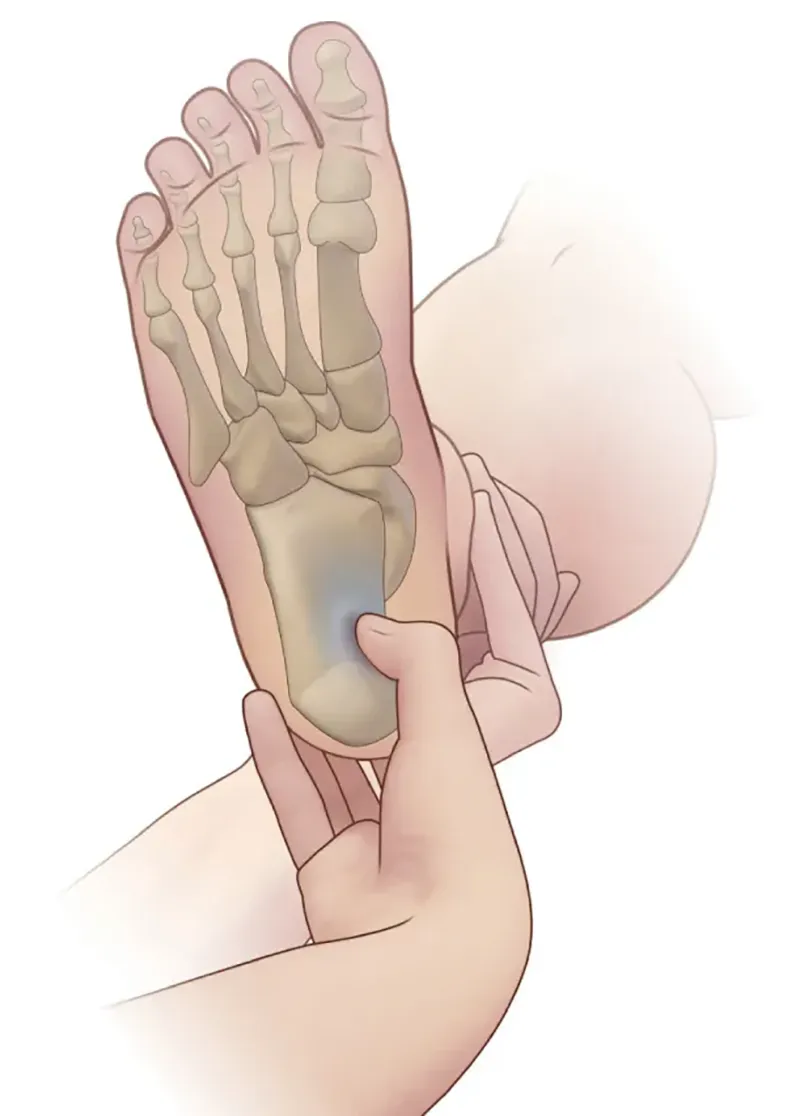

As is the case with the carpal tunnel, space within the tarsal tunnel is relatively limited with very little capacity for expansion. This space can be further restricted by both extrinsic and intrinsic factors. Extrinsic factors (restricting forces from outside the tunnel) include improperly fitted shoes, generalized edema from trauma or chronic conditions, posttraumatic or postsurgical scarring, and postural or anatomical abnormalities such as pes planus. Intrinsic factors (restricting forces within the tunnel) include tendinopathy, tenosynovitis, osteophytes, soft-tissue fibrosis, and space-occupying etiologies like ganglion cysts, varicose veins, lipomas, or tumors. All these factors can create compression of the posterior tibial nerve, medial plantar nerve, or lateral plantar nerve within the tarsal tunnel.

Nerve compression within the tarsal tunnel is referred to as tarsal tunnel syndrome or posterior tibial neuralgia and presents as burning pain or numbness in the associated area that occurs spontaneously or with movement and/or weakness or atrophy in the associated muscles. As is the case with carpal tunnel syndrome, nerve dysfunction is often progressive and can become permanent if left untreated. It can be more challenging to treat the tarsal tunnel as it is an integral part of the weight-bearing architecture of the lower extremity and significantly less common than carpal tunnel syndrome. A comprehensive assessment of both extrinsic and intrinsic factors is required in order to determine proper treatment.